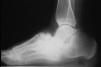

Artritis reumatoidea. En la artritis reumatoidea se afecta el tarso, de forma equivalente a la afección del carpo, y habitualmente de forma concomitante a la afección de las articulaciones metatarsofalángicas. Suele ser una afectación bilateral y simétrica. La localización más frecuente es en la porción astragaloescafoidea de la articulación astragalocalcaneoescafoidea, que se afecta en aproximadamente un 30% de los pacientes (fig. 12), la articulación subastragalina en un 23% de los casos (fig. 13), la escafocuneana en un 20% y la metatarsocuneana en un 15% (fig. 14)10. La radiografía muestra inicialmente osteopenia y pinzamiento de las interlíneas articulares con esclerosis focal, mientras que las erosiones de las superficies óseas son pequeñas y escasas. La afección del tarso es progresiva con la duración de la enfermedad y comporta un pie plano, que se incrementa marcadamente después de 3 o 4 años de evolución de la enfermedad10,11. En los casos de larga evolución se puede observar anquilosis de todo el tarso, que puede acompañarse de pequeños osteófitos en esta región dorsal del pie (fig. 15).

Figura 13. Artritis reumatoidea, con afectación de la articulación subastragalina y astragaloescafoidea.